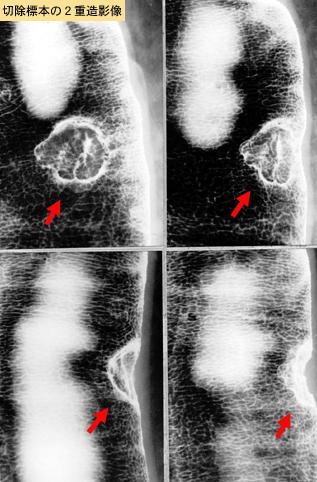

clasificación del pacienteTumor Epitelial Maligno/Adenocarcinoma

parte(separada por órganos)colon/sigmoides

método de exámenRayos X

clasificación ectoscópica de tumoresTipo 2(Tipo ulcerado de bordes claros)/

diámetro mayor del tumor10 - 14

grado de penetraciónmp